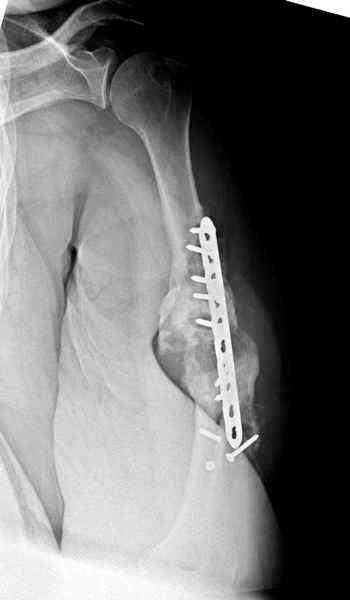

Когда разбирался случай на сайте, и у нас была больная с похожей

патологией, ложный сустав после поперечного перелома, леченного год

назад где-то и кем-то в другом месте.

Первичную пластину убрали недели 6 назад из переднего оригинального

доступа, и из-за подозрительности тканей вокруг пластины, решили

провести реконструкцию поэтапно.

Хотя сам не стороннник применения более массивных имплантов для

плеча, но для этого случая сделали исключение. На снимке 4А диаметр

мягких ткани около 20 см, при весе больной более 135 кг, и также

выступление Андрея Волны подстегнуло к применению более массивной 4.5

мм локинг пластины.